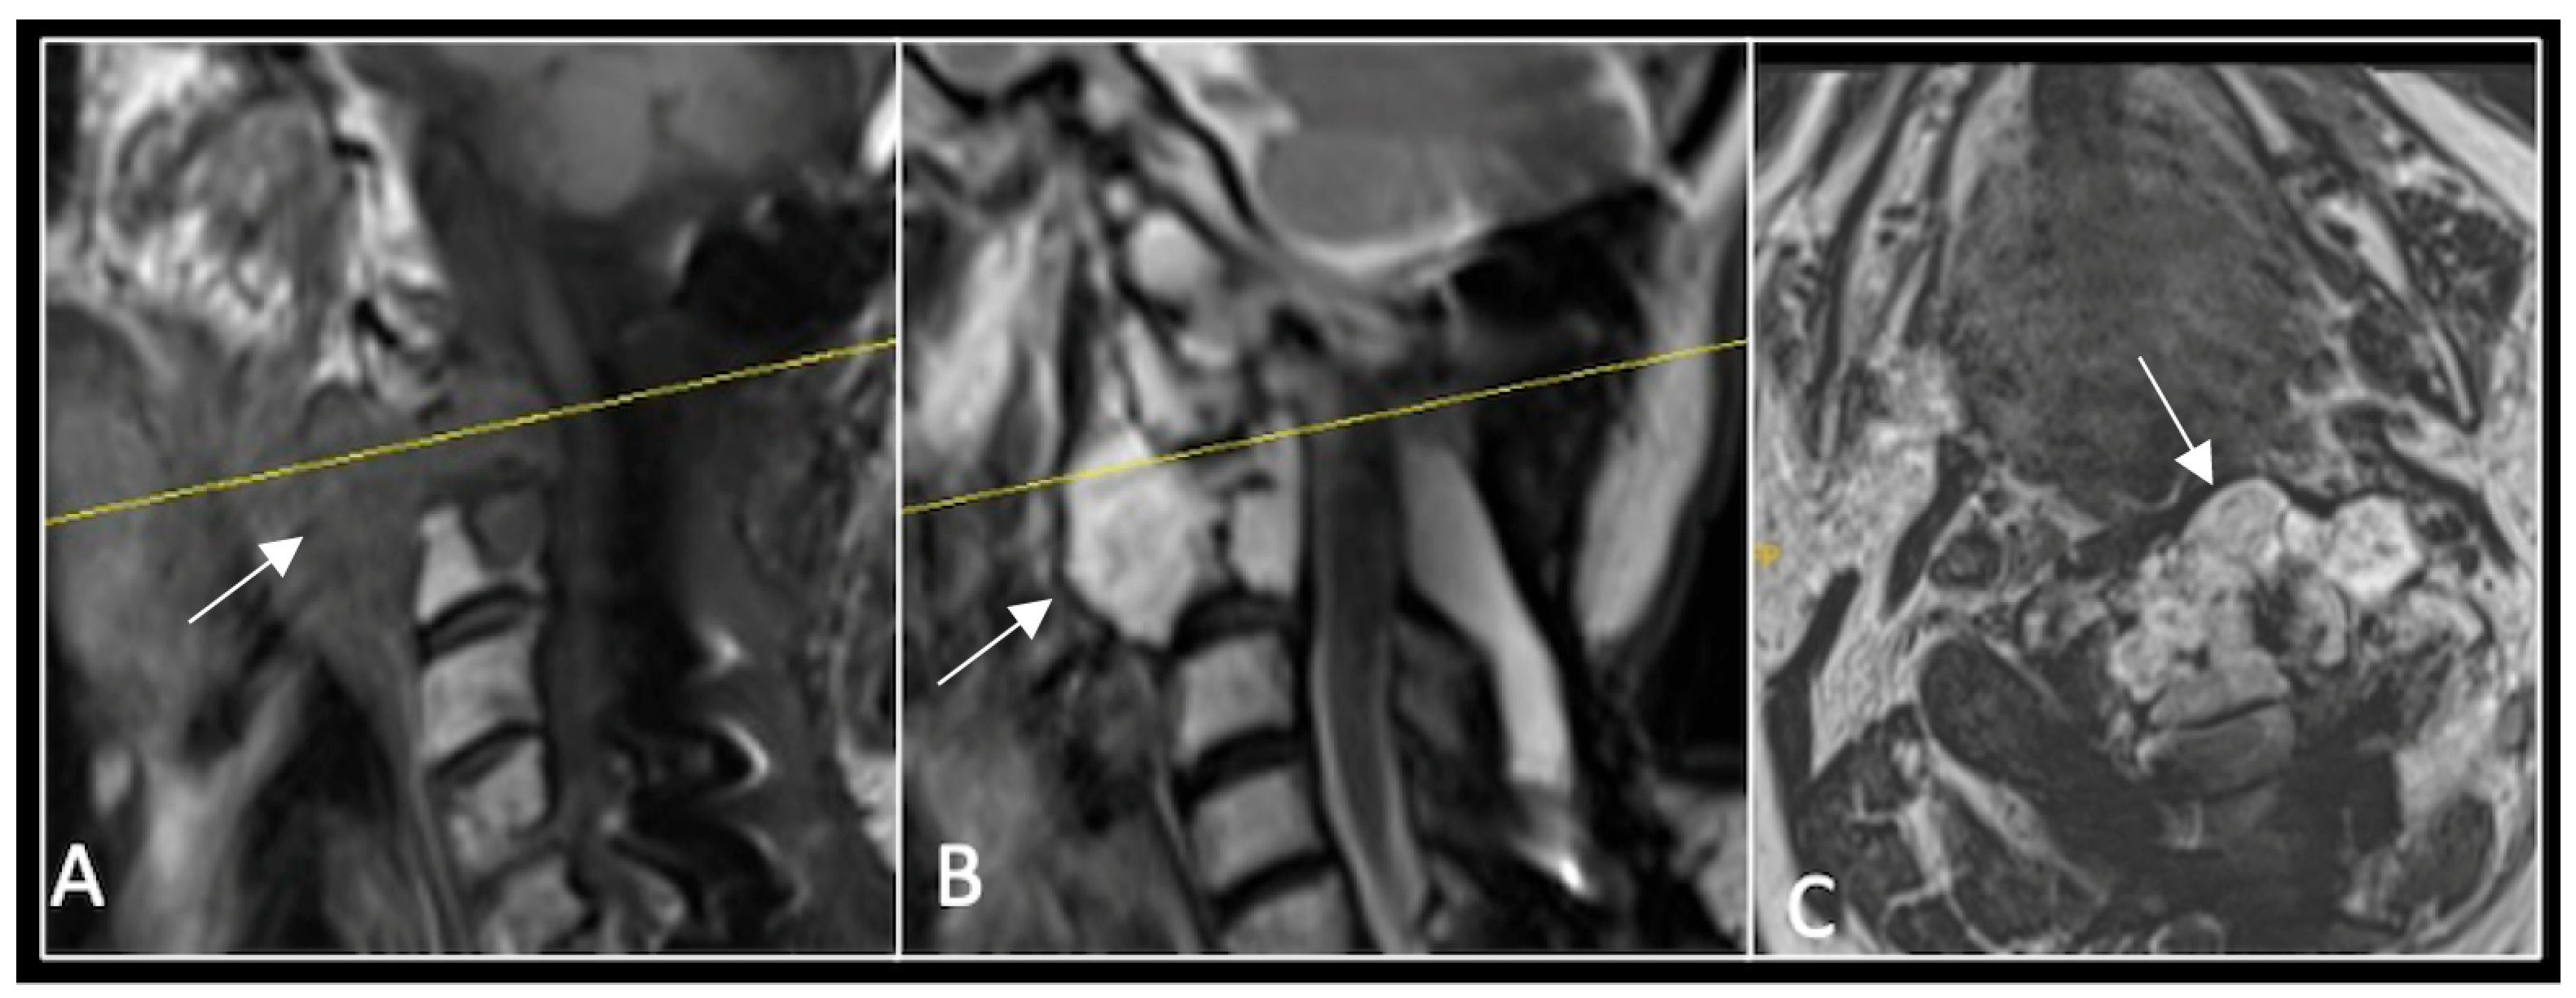

A 73-year-old male presented with an eight-month history of neck pain that was exacerbated on lying flat. He denied any symptoms of myelopathy and radiculopathy. He did not have any constitutional symptoms of malignancy. Past medical history included hypertension, renal cysts, and an ascending thoracic aneurysm. Examination was unremarkable. Diagnostic whole-spine MRI imaging demonstrated a large lobular mass localised to the cervical spine (Figure 2). Biopsy confirmed a conventional chordoma, and he underwent separation surgery followed by adjuvant proton beam therapy. Postoperative surveillance imaging at 12 months demonstrated stable disease (Figure 3).

Figure 3.

RI post-separation surgery showing reduction in tumour (arrow) dimensions and circumferential decompression. The posterior elements have been removed, and a posterior occipitocervical stablilsation has been performed. En-bloc resection would have necessitated sacrificing the left C2 nerve root and vertebral artery. The yellow line on the sagittal images indicates the level of the corresponding axial section. (A) T2W sagittal; (B) T1W sagittal; (C) T2-W axial.